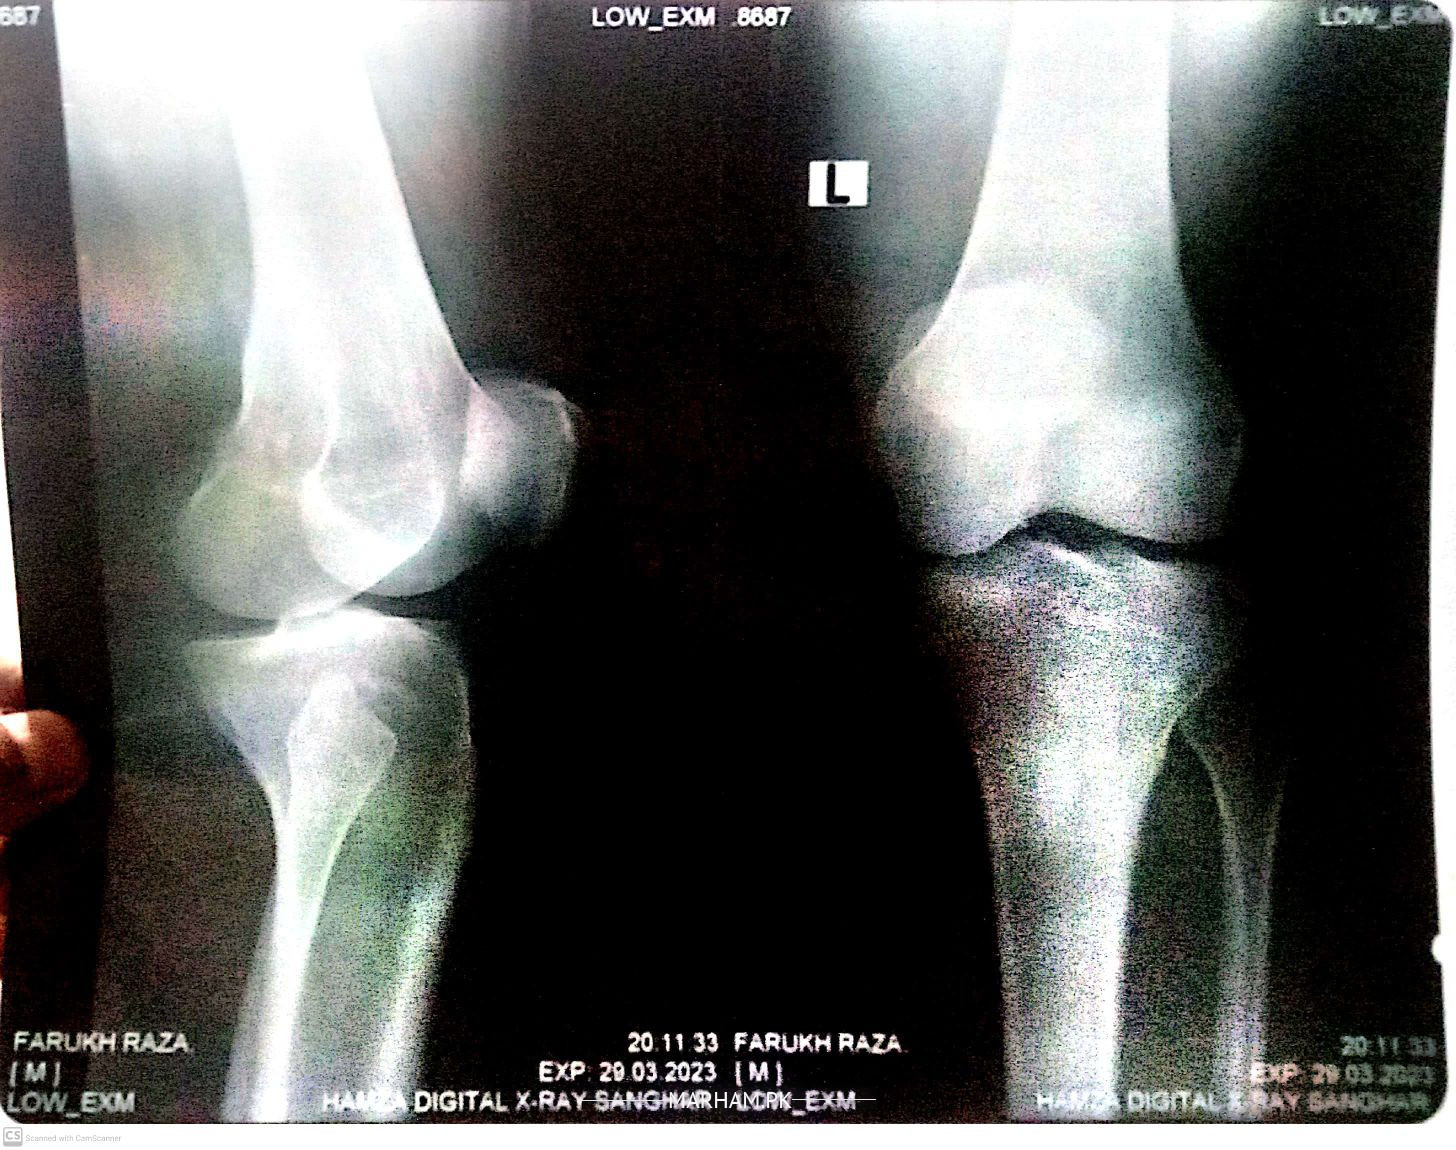

Mere left ghutne me dard hota he ghutna morne k bad seedha karte huwe shadeed dard hota he mene X-ray karwaya he any Orthopedic pls check this x-ray

osteoarthritis knee

Salam, you have arthritis of knee joint, it happens mostly because of age. you shall take painkillers and keep walking to strengthen your thigh muscles. if it gets very painful even with painkillers then you may need injection inside knee joint or total knee replacement (new knee joint). Thanks

u are suffering from osteoarthritis.

grade 2 osteoarthritis

as for x-ray is concern it only shows early signs of arthritis

your xray is normal. you just need some specific knee exercises and your problem will be solved.